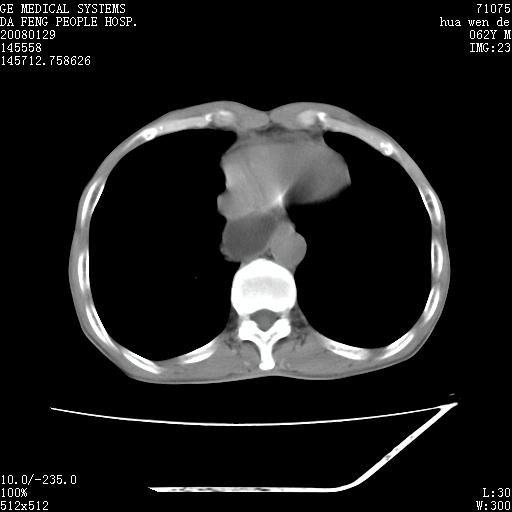

男性,67岁。作肺部检查时发现

1.整个食管扩张,未见明显占位性病变,贲门区亦未见明显占位病变,考虑:贲门失驰缓症;

2.右上肺病变边缘可见毛刺,囊壁厚度不均匀,周围境界较清楚,未见炎性渗出性影,右上肺外带可见片状影,边缘不清,考虑:肺癌伴空洞形成、右上肺炎。

15楼主分析有道理,胸腔胃除外,那么考虑贲门失驰缓症并肺部化脓感染(吸入性)可能。

肺内病灶位于右肺中叶,食道扩张后导致咽部功能受影响,吸入气管可能是存在的。

可疑之处在于:左肺未见吸入性病灶存在。另右肺癌(右肺中央型并阻塞性肺炎)不能除外

食管全程扩张,壁均匀不厚,喷门失弛缓症

右上肺空洞可见液平,临近肺野磨玻璃密度,考虑1.结核2.脓肿

右上肺空洞可见液平,临近肺野磨玻璃密度,考虑1.结核2.脓肿 支持!